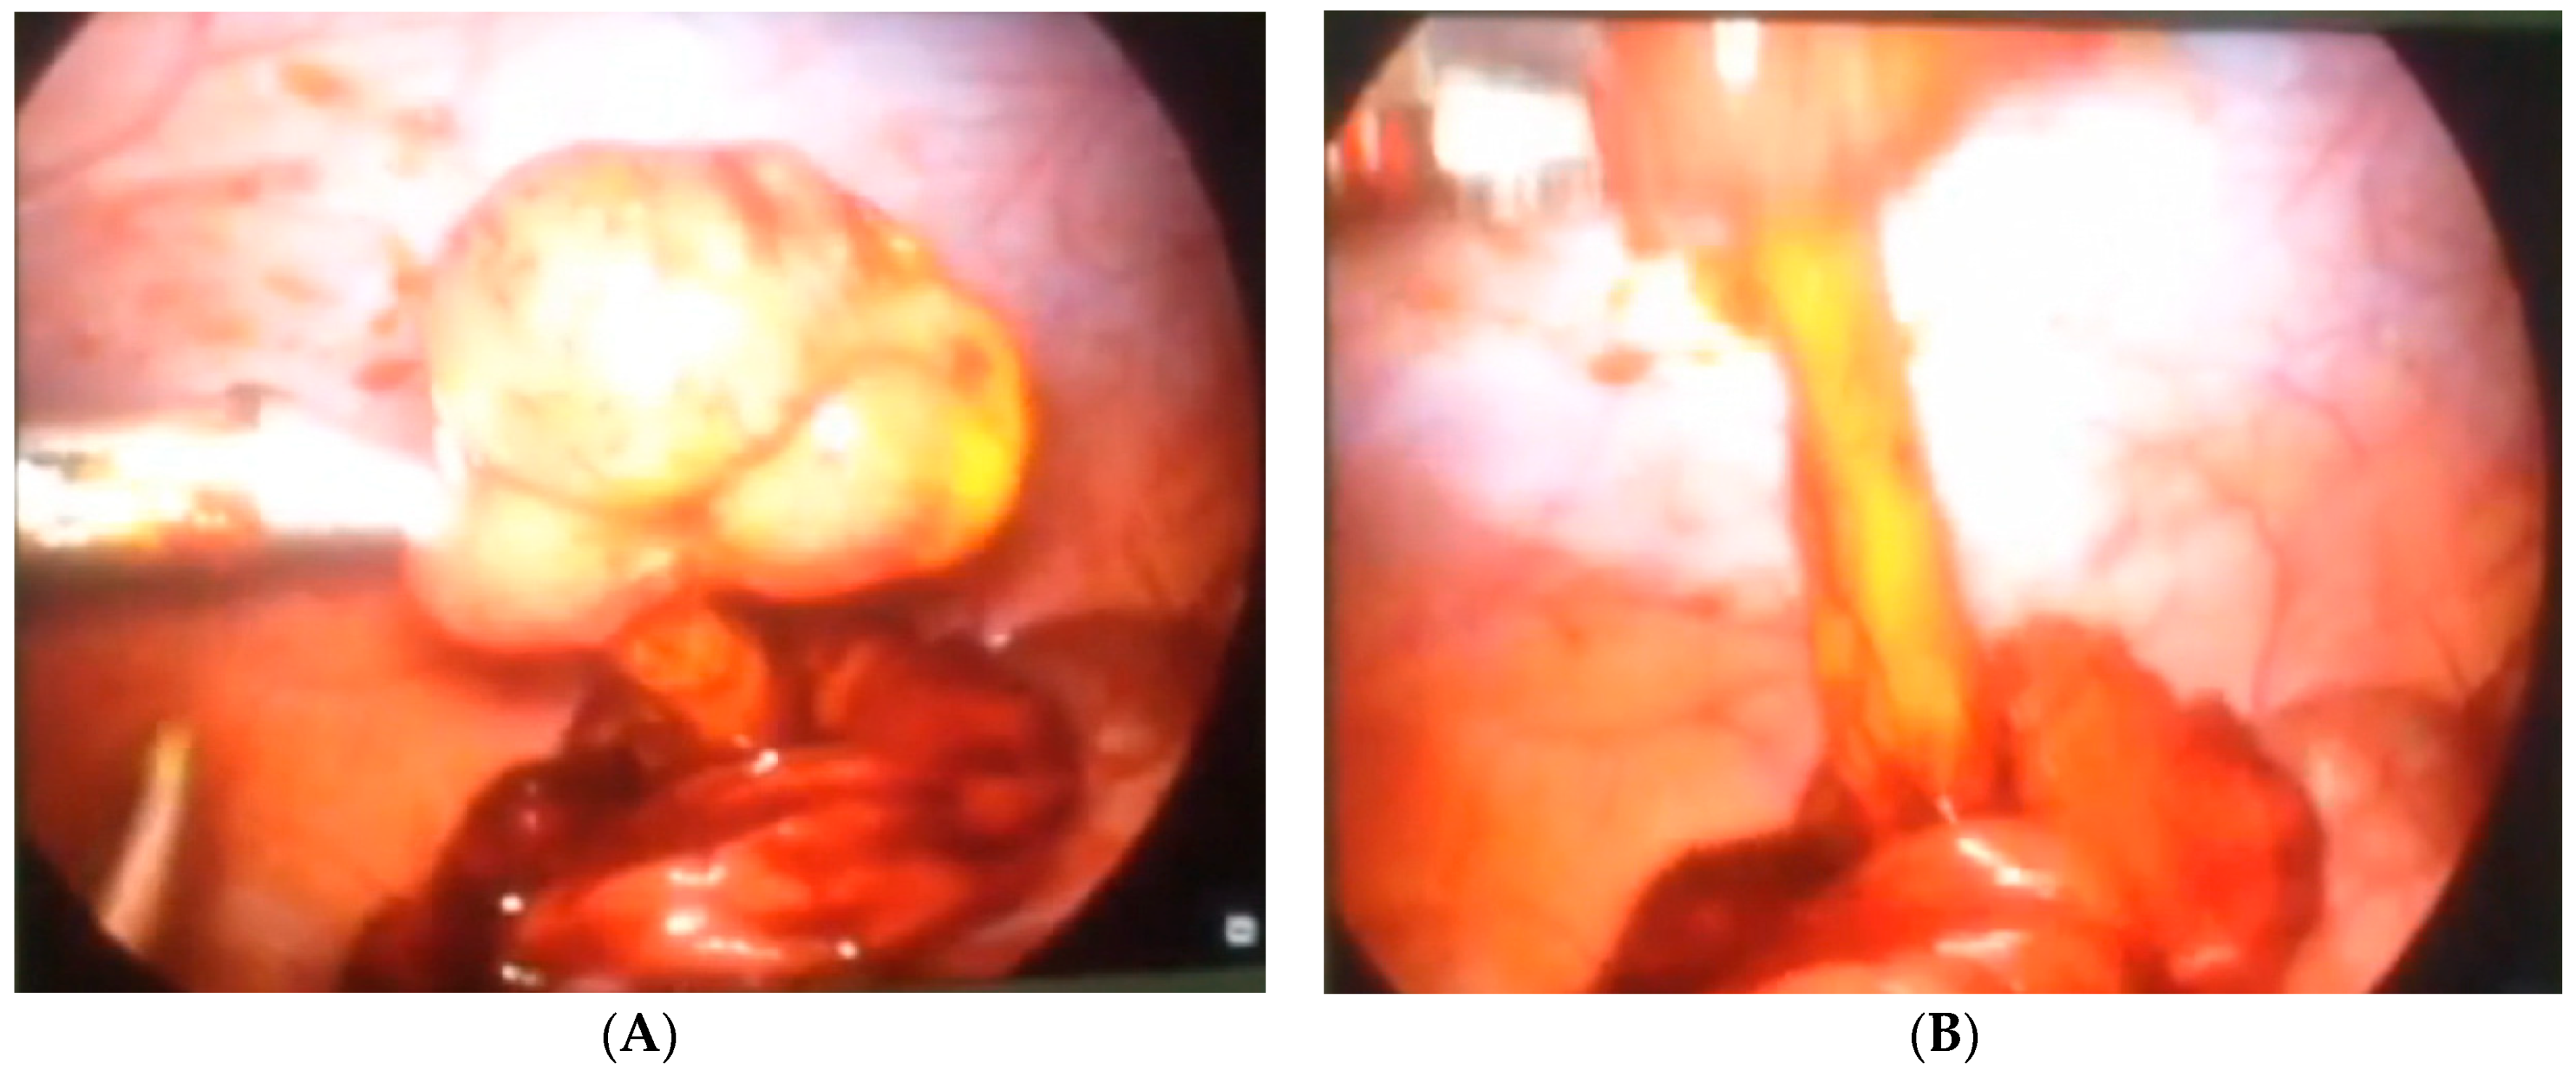

Our third case is a 2-year-old child who was admitted to hospital due to blood and mucus in the stool. Intraoperative colonoscopy revealed polypoid form diameter around 2 cm, 30 cm from the anocutaneous line that showed ulcerations and was on the wide base. Biopsies were sent for pathohistological examination. The endoscopic histologic diagnosis was a polyp of the sigma and chronic colitis. A polypectomy was performed using a laparoscopic–endoscopic “rendezvous” procedure. Infraumbilical open access with the 5-millimeter Hasson technique was used to create pneumoperitoneum. The working ports were placed in epigastric and in the upper right quadrant. By lighting from the lumen of the colon, an enterotomy was performed (Figure 1A). The polyp was visualized, resected in its base (Figure 1B), and sent for definitive pathohistological examination. A direct enterorrhaphy during the laparoscopy was performed in the standardized manner. The operation was completed, and the postoperative period was uneventful.

Figure 1.

(A) Endoscopic guidance from the lumen of the intestine and a place of enterotomy, (B) Complete visualization of the polyp and its resection.